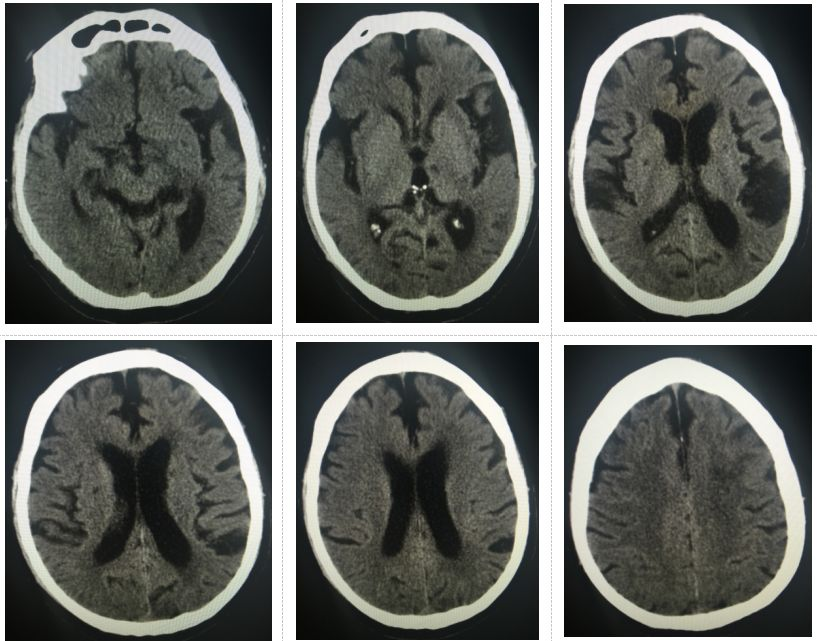

图6.术后次日头颅CT示颅内未见出血

术后为预防高灌注损伤,积极控制血压在110/70mmHg水平,并给予依达拉奉注射液清除自由基,继续双抗、他汀降脂及内科治疗,患者病情平稳,未出现新发神经系统症状及体征。术后次日,复查头颅CT示颅内未见出血及高灌注表现。患者血压逐渐调整至130/80mmHg水平,病情稳定,右侧肢体无力、麻木缓解,术后第3日顺利出院。

本例患者的诊治由最初的MRA提示左侧颈内动脉岩骨段狭窄,到彩超发现左侧颈内动脉起始部重度狭窄乃至闭塞改变,直至DSA才明确右侧椎动脉起始部狭窄及左侧颈内动脉起始部重度狭窄,导致颅内低灌注出现临床症状。通过本例患者,我们认为DSA是诊断脑血管病的金标准,虽然无创检查可以提示大部分的缺血性脑血管病,但由于血流动力学障碍导致的远端血管塌陷或假性狭窄乃至闭塞假象在临床中仍较常见。对于本例患者,高龄,左侧颈内动脉极重度狭窄,合并右侧椎动脉狭窄,若不能及时接受介入治疗,随时存在急性大血管闭塞出现恶性卒中的可能,但处理任何一处病变,均存在再灌注或过度灌注损伤的可能。因此,在治疗策略上,为避免颈动脉支架术后的窦反射或术后为预防过度灌注而采取控制性低血压时出现后循环缺血,应先期行右侧椎动脉支架成形,如此可避免后循环的缺血,在术后可以更加放心的控制血压。术后该患者血压控制在110/70mmHg左右,逐渐过渡至正常血压水平。术后次日复查CT未见出血及高灌注表现,患者右侧肢体无力、麻木缓解,术后第3日顺利出院。